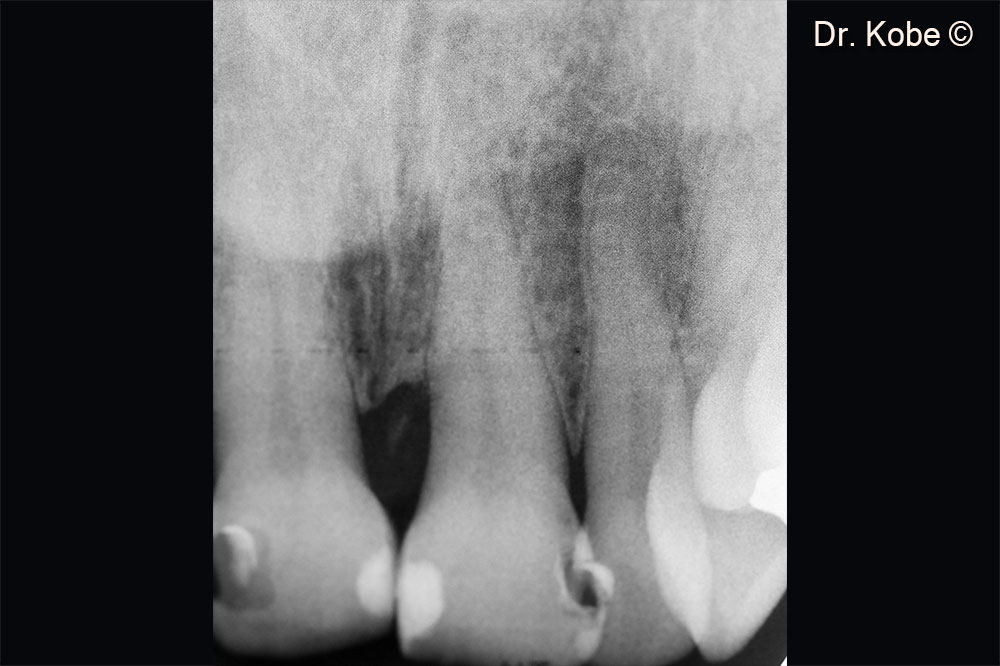

Khuyết tật theo chiều dọc có thể nhìn thấy trên phim chụp X-Quang

Hình ảnh X-Quang sau 1 năm điều trị